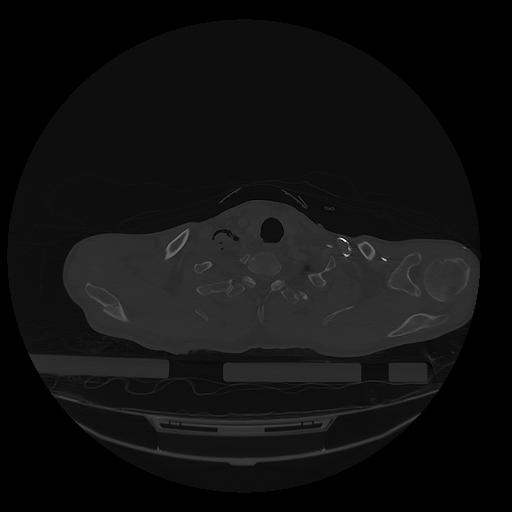

31 PULMON,CE,Vol,1.0,PULMON,,